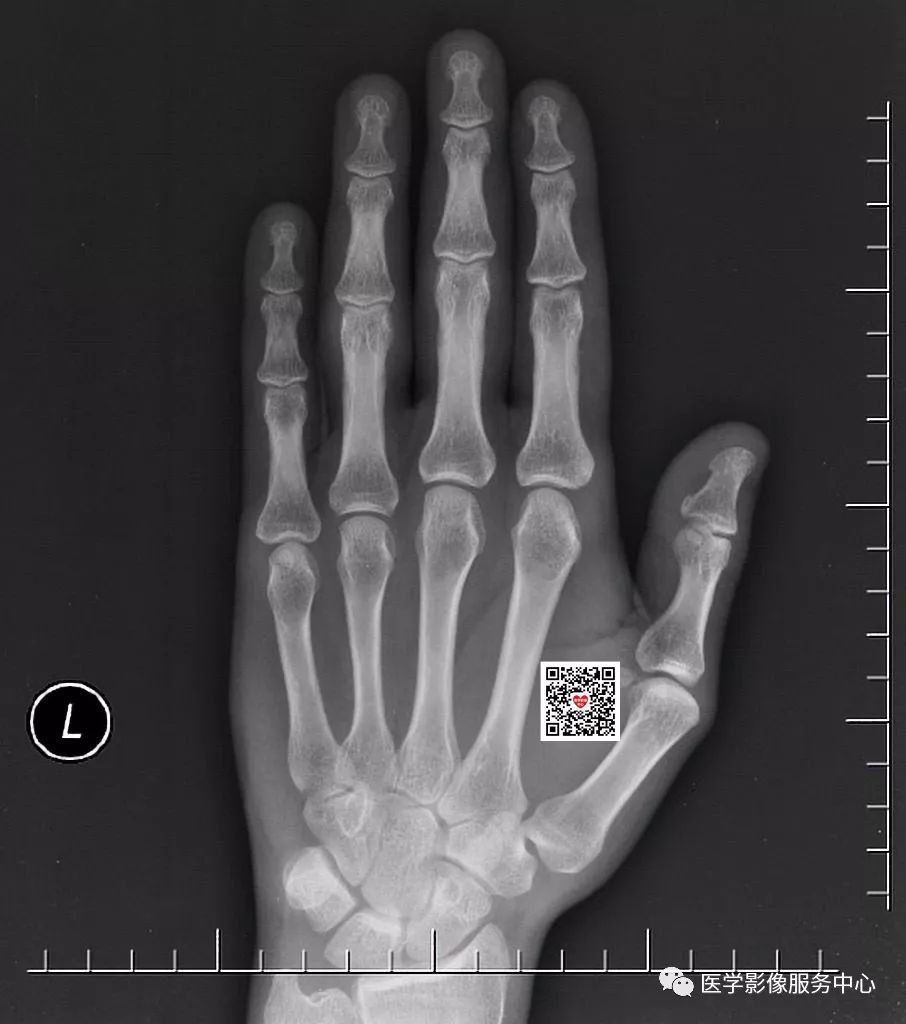

假设申请单仅写外伤摄片,你能发现什么问题?

在这张正位片上,大家有没有发现问题?请仔细看哦!

有些外伤检查申请单上仅仅写外伤摄片,没有说明具体的受伤部位,这样的申请单是不符合规定的。以本病例来看,如果没有详细病史的话,一些经验不足的诊断医生可能会漏诊。就算有经验的诊断医生,在紧张繁忙的工作中,如果出现一丝精神倦怠,很有可能会忽略这种小的骨折线。所以,详细的检查申请单是减少漏诊误诊的必备条件。如果本病例申请单提示外伤位于左手第三指和第四指,相信大家都会重点观察受伤处并做出正确诊断。

2、标准的摄片摆位很重要

标准的摄片摆位是正确诊断的前提。但在实际工作中,由于患者伤处疼痛,往往配合不佳。这时候技术员朋友需要尽量的按照标准体位摆放,多给患者一些准备时间,不要因为可能会耽误时间而应付了事。以本病为例,正位片很难看到骨折线影,只有在斜位片才能够清楚发现两处骨折。假如患者因为疼痛,斜位摆放位置不佳,有可能将骨折线遮掩,从而得不到正确的检查结果。

3、影像诊断的经验性很重要

一个称职的影像诊断医生,要注意影像的蛛丝马迹。本病例的正位片虽然看不到明显的骨折线影,但是第四近节指间关节周围软组织还是可以发现肿胀。斜位片更加明显,第三、第四近节指间关节周围软组织均可发现肿胀,这就给我们一个提示。这时候要仔细查看该处有无骨折存在。这种间接征象对影像诊断有很大帮助。此外,正位片看不到异常,不代表没有问题,有时我们的诊断同行正位片没发现异常,很自信的认为没有问题,匆匆扫一眼斜位片,然后直接得出未见骨折的错误诊断。正位片与斜位片都很重要,要结合看,这也是影像检查要拍摄正位及斜位的原因。

一份合规的检查申请单、一个标准的摄片摆位、一次细心的读片诊断,三者均做到的结果就是能够得出一份对患者负责、让患者满意的检查结果。